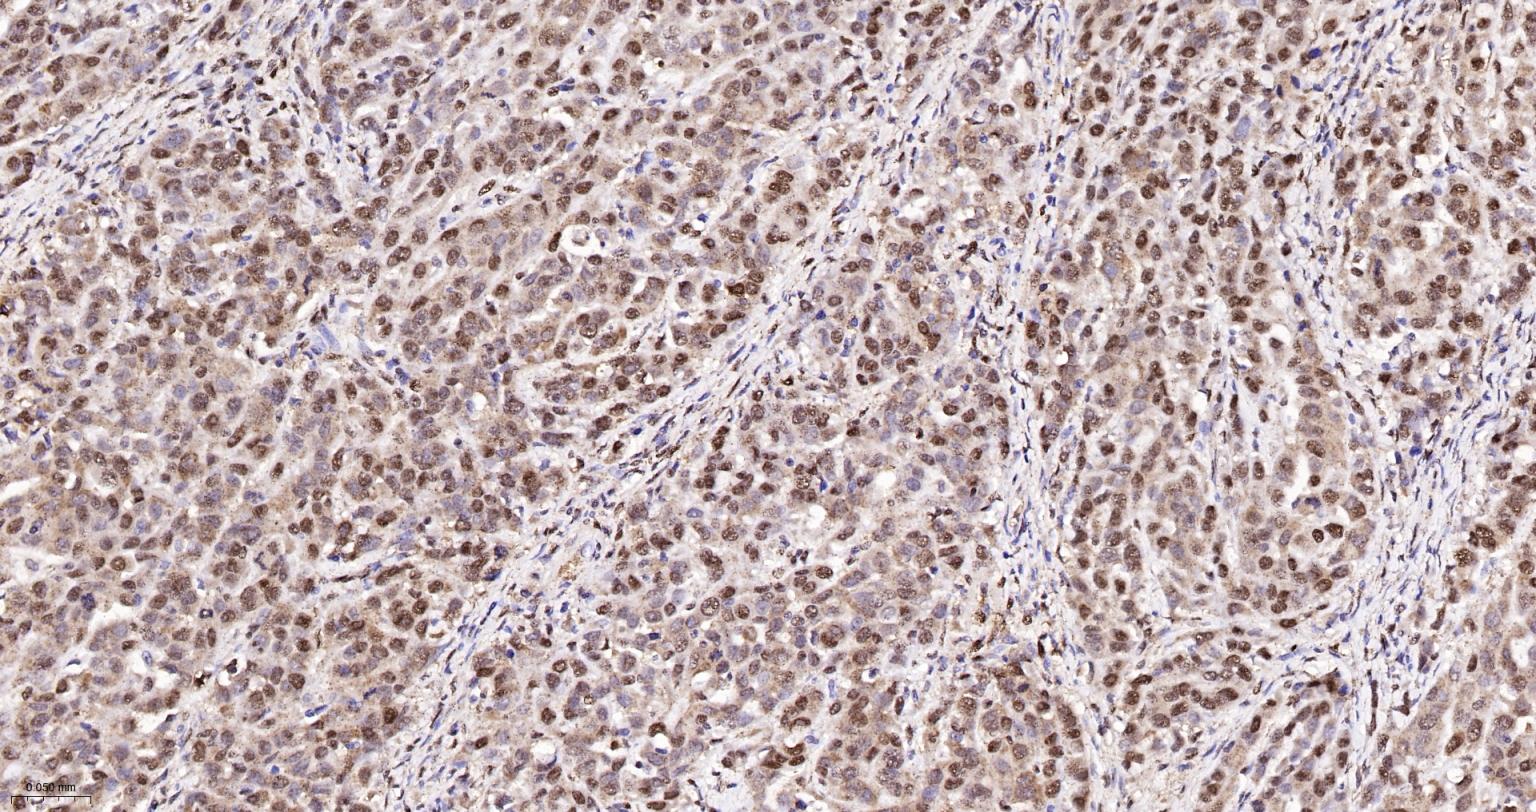

Paraformaldehyde-fixed, paraffin embedded Human Breast Cancer; Antigen retrieval by boiling in sodium citrate buffer (pH6.0) for 15 min; The section was incubated with APEX1 Monoclonal Antibody, Unconjugated (bsm-60707R) at 1:200 overnight at 4°C, followed by conjugation to the bs-0295G-HRP and DAB (C-0010) staining.